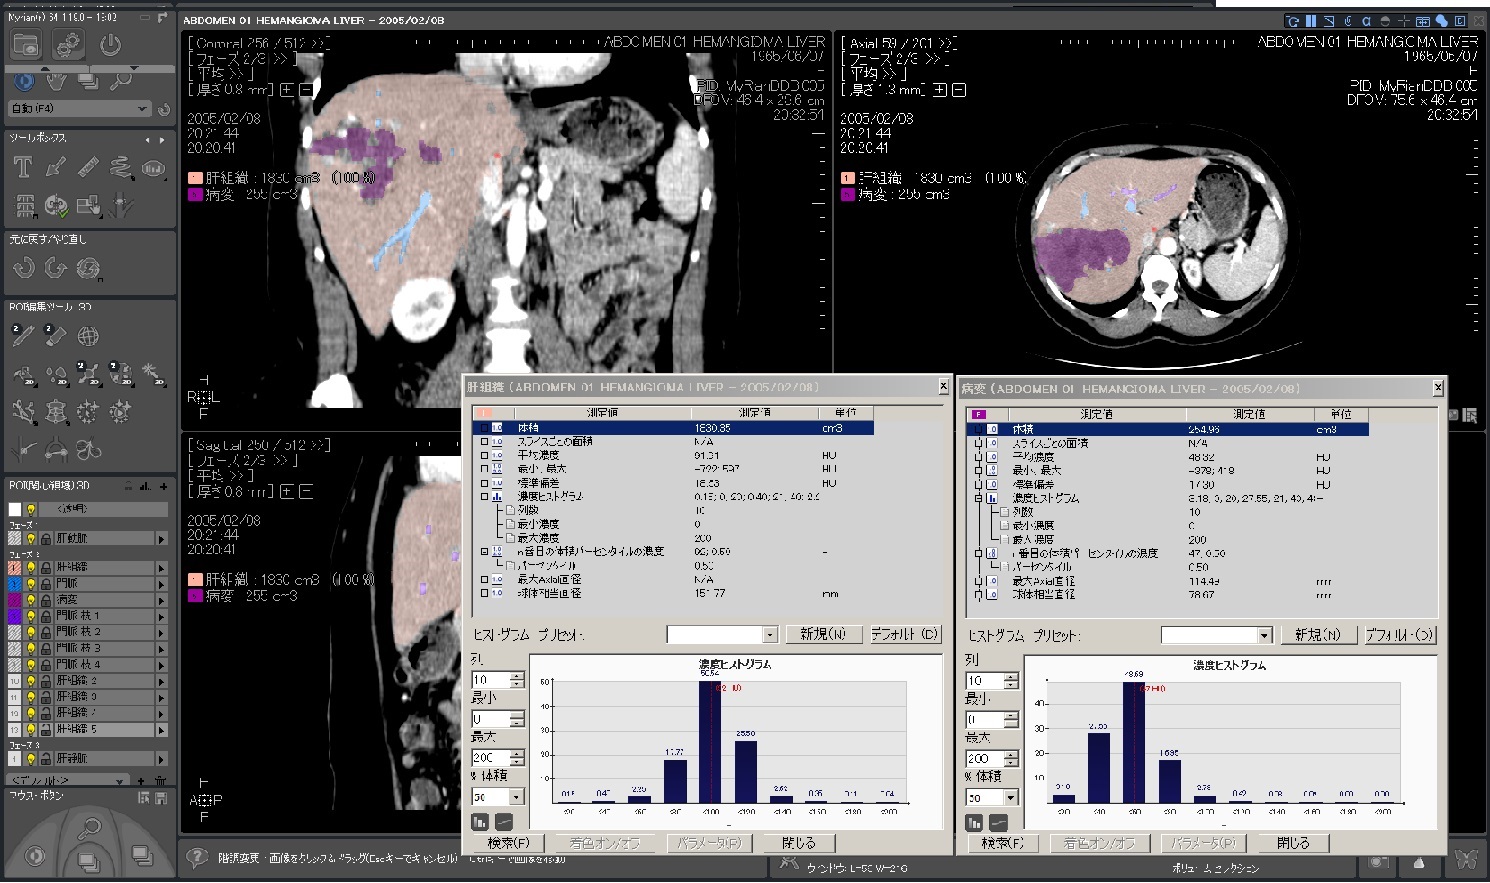

Myrian®XP-Liver 肝臓アプリケーション

世界的な実績と評価を得ている、肝臓解析と手術計画用ソフトウェア

独自に開発された、正確な非剛体レジストレーションと優れたセグメンテーション・アルゴリズムにより肝血管系、肝実質、腫瘍などを数秒で抽出します。

| 1.病変部領域 正常部領域の ワンクリック セグメンテーションと 体積表示 |

| 4.ヒストグラム解析 |  |